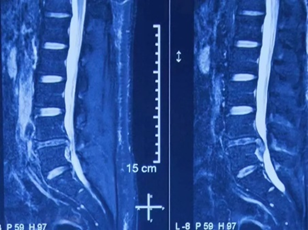

39 岁的患者王先生(化名)深受腰腿麻痛的困扰,一开始是换体位时腰痛难忍,后来逐渐加重,痛到不能走路。医生诊断他是腰椎滑脱继发椎管狭窄症,要做个微创手术。

"很多人认为微创只是切口小,这是片面的。"刘艺明主任表示,真正的微创是内外兼修。不仅患者肉眼可见的手术创口小,患者看不见的创伤比如术中的组织分离、肌肉牵拉都要降到最低,这对术后的恢复至关重要。

刘艺明为患者设计微创的腰椎内固定手术方式:微创经椎间孔入路腰椎椎间融合术(MIS-TLIF),在提高手术效果的前提下,手术切口只有 3 cm,对腰部肌肉的牵拉、剥离程度小,手术时间不到 1 个小时。